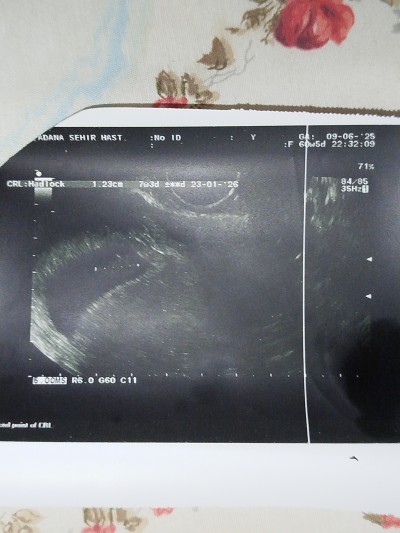

9 Haziran Hamilelik Dönemi Genel kategorisinde (445 puan) sordu

image

tahmin etmek isteyen etsin saçma bulanların sayfama bakmasın hepimizin hamileyiz kalp kırmaya gerek yok

Haftanız çok erken tahmin için ama kese yuvarlaksa kız uzun fasulye şeklindeyse erkek diyorlar tabi bu da bir hurafe